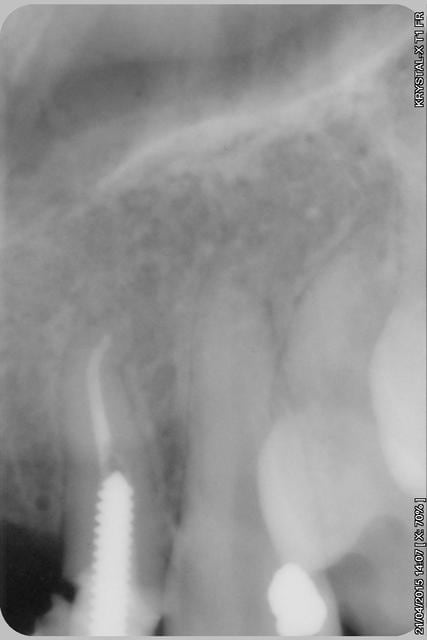

étonnant en effet... et encore plus étonnant, ce qui n'arrive jamais le radiologue (qui est parfaitement compétent normalement) a inversé la droite et la gauche.

le scan n'est pas terrible, mais suffisant pour voir que 22 une fois extraite, ne va pas etre simple à implanter, par contre 11/21 avec un peu d'expansion...